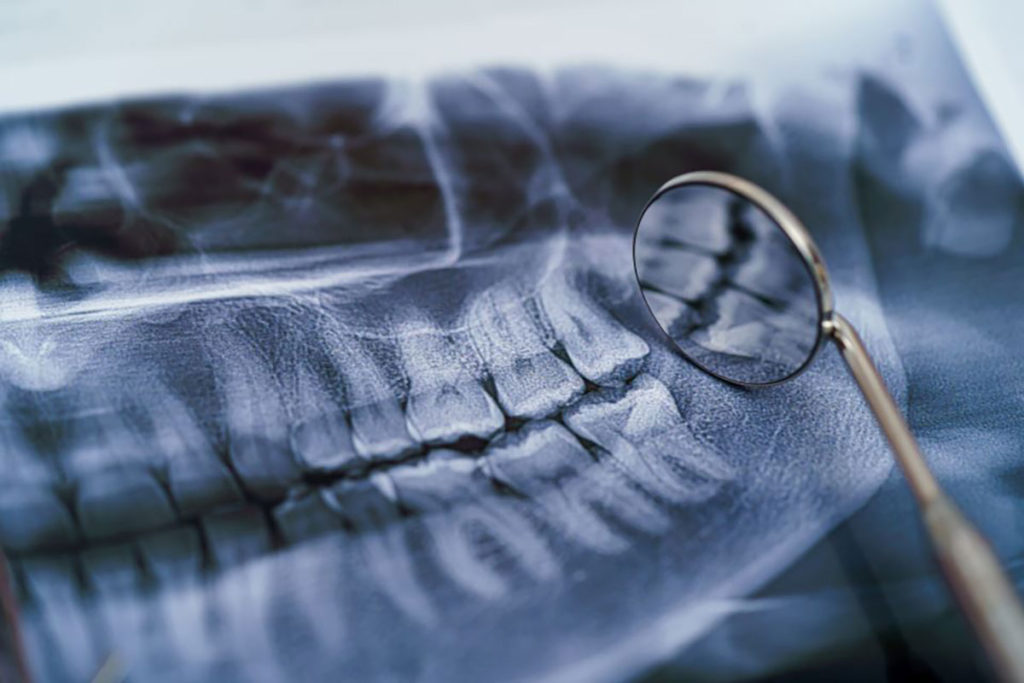

radiografie dentara panoramica

Radiografie panoramica

Radiografia dentara panoramica este un instrument folosit adesea in stomatologia moderna, atat in vederea stabilirii unui diagnostic, cat si a unui plan de tratament. Aceasta ne permite sa obtinem o imagine de ansamblu a intregii cavitati bucale si sa depistam probleme si afectiuni care nu ar putea fi descoperite in urma unui examen obisnuit.

Exista mai multe tipuri de radiografii dentare si este firesc sa va intrebati ce inseamna radiografie panoramica. Cunoscuta si sub denumirea de ortopantomografie, radiografia panoramica este o metoda de investigatie ce permite vizualizarea in ansamblu a dentitiei (tuturor dintilor) si a elementelor maxilo-faciale inconjuratoare (osul maxilar si mandibula, sinusul maxilar, articulatiile temporo mandibulare).